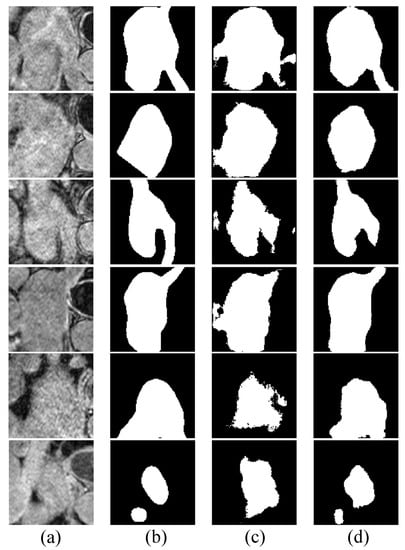

4.3. Results on Late Gadolinium Enhancement MRI